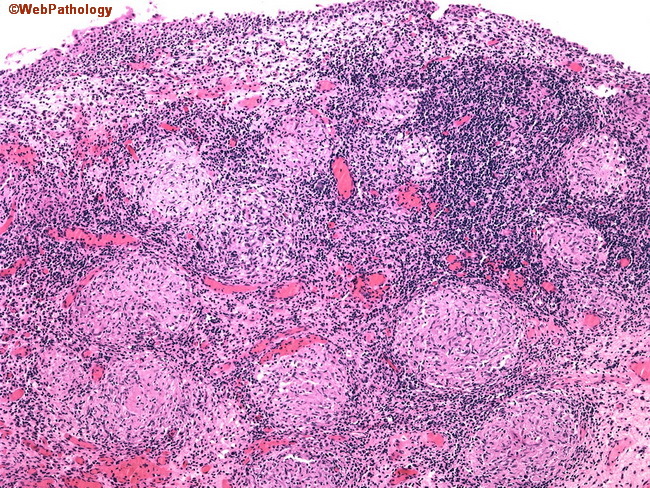

Granulomatous cystitis

In theory could be caused by TB, or even schistosoma, but nowadays is mostly seen secondary to BCG chemotherapy for urothelial carcinoma (intracystic injection of the BCG vaccine).